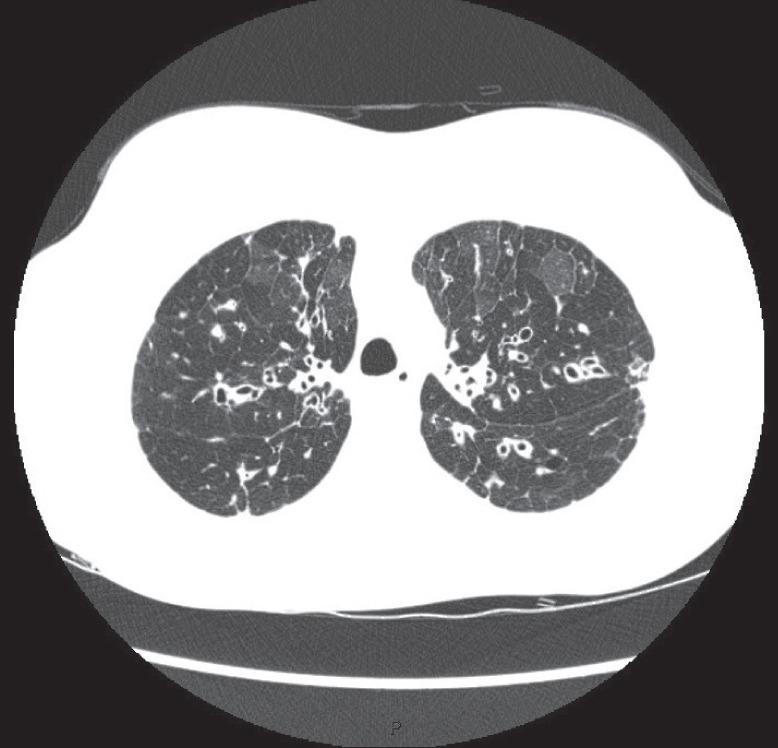

To recognise the clinical and radiological presentation of the spectrum of diseases associated with bronchiectasis.To understand variation in the aetiology, microbiology and burden of bronchiectasis and cystic fibrosis across different global healthcare systems.

Bronchiectasis is the term used to refer to dilatation of the bronchi that is usually permanent and is associated with a clinical syndrome of cough, sputum production and recurrent respiratory infections. It can be caused by a range of inherited and acquired disorders, or may be idiopathic in nature. The most well recognised inherited disorder in Western countries is cystic fibrosis (CF), an autosomal recessive condition that leads to progressive bronchiectasis, bacterial infection and premature mortality. Both bronchiectasis due to CF and bronchiectasis due to other conditions are placing an increasing burden on healthcare systems internationally. Treatments for CF are becoming more effective leading to more adult patients with complex healthcare needs. Bronchiectasis not due to CF is becoming increasingly recognised, particularly in the elderly population. Recognition is important and can lead to identification of the underlying cause, appropriate treatment and improved quality of life. The disease is highly diverse in its presentation, requiring all respiratory physicians to have knowledge of the different "bronchiectasis syndromes". The most common aetiologies and presenting syndromes vary depending on geography, with nontuberculous mycobacterial disease predominating in some parts of North America, post-infectious and idiopathic disease predominating in Western Europe, and post-tuberculosis bronchiectasis dominating in South Asia and Eastern Europe. Ongoing global collaborative studies will greatly advance our understanding of the international impact of bronchiectasis and CF.

认识与支气管扩张相关疾病谱的临床和影像学表现。理解不同全球医疗体系中支气管扩张和囊性纤维化在病因、微生物学及疾病负担方面的差异。

支气管扩张是指支气管扩张,通常为永久性扩张,并伴有咳嗽、咳痰及反复呼吸道感染的临床综合征。它可由一系列遗传性和获得性疾病引起,也可能本质上是特发性的。在西方国家,最广为人知的遗传性疾病是囊性纤维化(CF),这是一种常染色体隐性疾病,可导致进行性支气管扩张、细菌感染和过早死亡。由CF引起的支气管扩张和由其他病症引起的支气管扩张在国际上对医疗体系造成的负担都日益加重。CF的治疗正变得越来越有效,导致更多有复杂医疗需求的成年患者。非CF引起的支气管扩张越来越受到重视,尤其是在老年人群中。识别很重要,可导致找出潜在病因、进行适当治疗并改善生活质量。该疾病的表现形式高度多样,要求所有呼吸内科医生了解不同的“支气管扩张综合征”。最常见的病因和表现综合征因地域而异,非结核分枝杆菌病在北美某些地区占主导,感染后和特发性疾病在西欧占主导,而结核后支气管扩张在南亚和东欧占主导。正在进行的全球合作研究将极大地推进我们对支气管扩张和CF国际影响的理解。